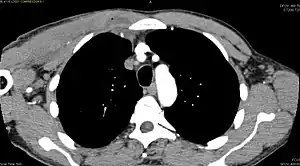

CT with IV contrast showing enlargement and heterogeneous hypodensity in the right pectoralis major muscle. A focal abscess collection with gas within it is present medially. There are enlarged axillary lymph nodes and some extension into the right hemithorax. Note the soft tissue and phlegmon surrounding the right internal mammary artery and vein. The patient was HIV+ and the pyomyositis is believed to be due to direct inoculation of the muscle related to parenteral drug abuse. The patient admitted to being a "pocket shooter"- CT exam showing a multiloculated fluid collection in the left gluteus minimus muscle found to be a staph aureus pyomyositis in a 12-year-old healthy boy.